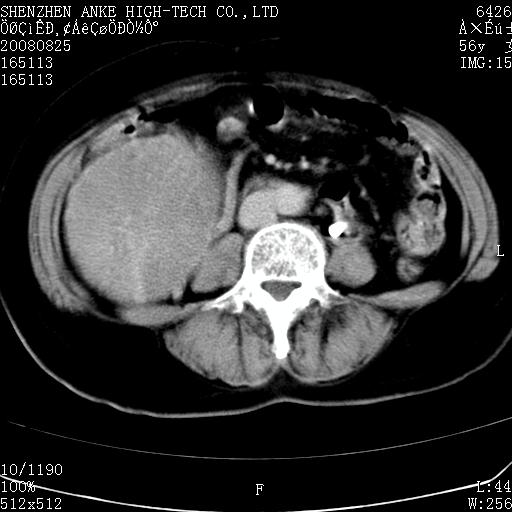

患者,女性,56岁,腰痛3年,查:右腹部约8x10cm肿块,固定,无压痛;8月23日在外院做了平扫,发现右肾巨大肿块(外院具体诊断不祥);今天在我院做了静脉肾盂造影,示:右肾明显增大,分泌功能明显减弱。

1)考虑右肾癌并右肾静脉瘤栓形成。2)脂肪肝。